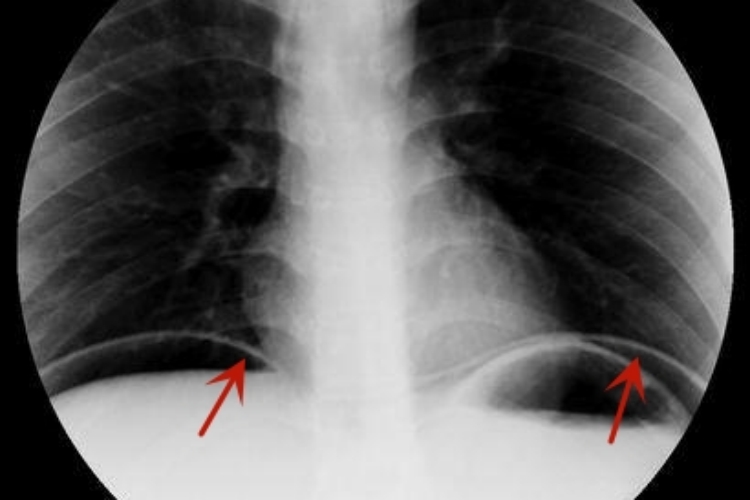

肠穿孔常表现为持续性的腹痛,腹部X线可发现膈下有游离气体,单侧或双侧,表现为线条状、新月状的透亮影,边缘清楚。

肠穿孔的主要X线征象为腹腔内游离气体,立位X线检查可见膈下游离气体,单侧或者双侧,表现为线条状、新月状的透亮影,边缘清楚。右侧透亮影的下缘为致密光滑的肝脏影,左侧新月状透亮影下内为胃泡影,外下方为脾脏影。大量气腹时可见双膈位置升高,内脏向下、内移,从而衬托出肝、脾、胃等脏器的外形轮廓。